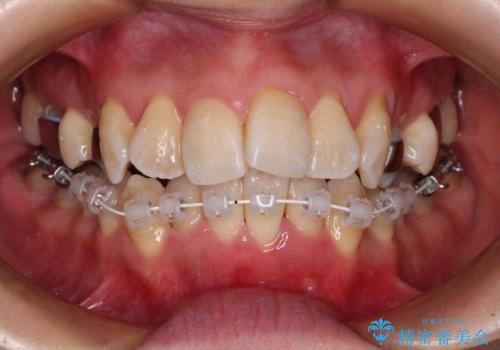

2. 治療途中

2. 【モニター】急速拡大装置 狭い歯列を拡大してワイヤー装置で短期間治療の治療中

2.